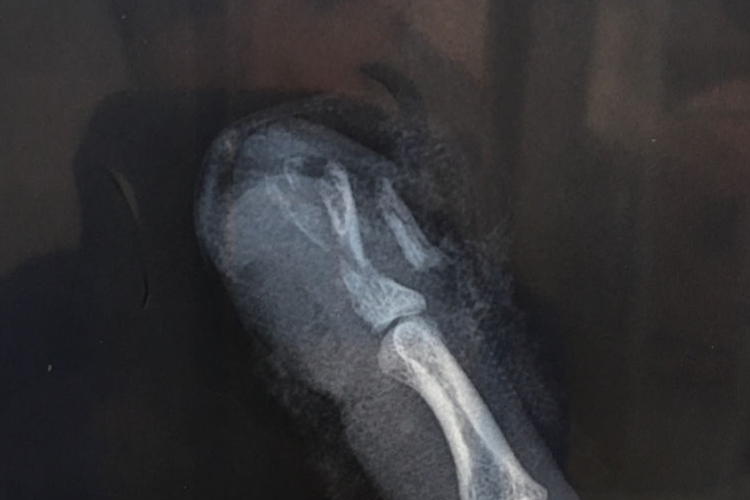

宝宝手指被门夹了若伤势较轻,可能并无明显症状,也不影响手指活动,可暂时观察。若伤势较重,可能导致软组织损伤,出现皮肤破损、肿胀,并伴有出血、淤血、疼痛等症状。若同时伴有局部畸形、反常活动、骨擦音或骨擦感等症状,则怀疑伤指可能出现骨折。

手术治疗:宝宝手指被门夹伤后,明确出现肌腱断裂、手指骨折等情况,考虑进行手术治疗。